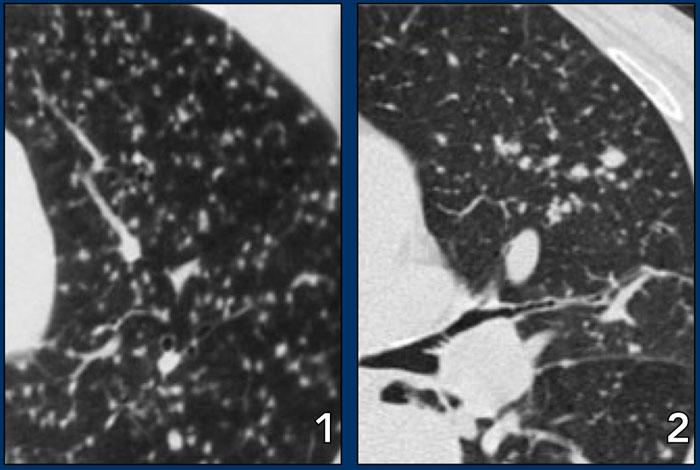

Dưới đây là hai ví dụ về viêm phổi quá mẫn bán cấp.

Có thể thấy các nốt trung tâm tiểu thùy bờ không rõ dạng kính mờ.

Đây là một trường hợp khác của viêm phổi quá mẫn bán cấp.

Có thể thấy hình mờ mờ nhạt ở trung tâm các tiểu thùy thứ cấp (mũi tên) với vùng dưới màng phổi được bảo tồn.

Hình ảnh HRCT này cũng cho thấy hình mờ trung tâm tiểu thùy mờ nhạt ở bệnh nhân HP bán cấp.

Lưu ý ranh giới không rõ của các nốt trung tâm tiểu thùy này.

Đôi khi các hình mờ trung tâm tiểu thùy có hình thái dạng nốt rõ hơn như trong trường hợp này.

Đây là một trường hợp khác của viêm phổi quá mẫn.

Có hình ảnh khảm.

Một số tiểu thùy thứ cấp biểu hiện kính mờ do thâm nhiễm phổi, trong khi các tiểu thùy khác sáng hơn do viêm tiểu phế quản với bẫy khí.

Bệnh nhân này nhập viện với triệu chứng khó thở cấp tính và phim X-quang ngực bình thường (không trình bày).

HRCT lúc nhập viện (trái) cho thấy các vùng kính mờ theo phân bố tiểu thùy.

HRCT kiểm tra mười ngày sau (phải) cho thấy các tổn thương đã thoái lui hoàn toàn mà không cần điều trị.

Các tổn thương được cho là do viêm phổi quá mẫn.